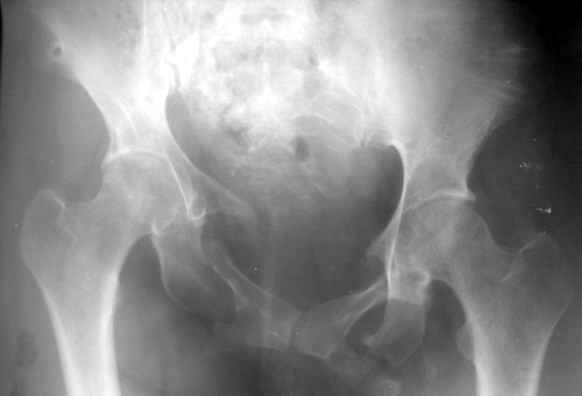

Застарелая деформация таза |

Вопрос Уральскому Пельвиоцентру: через год после травмы, довольно симпатичная женщина, болей нет, только ходит призрамывая на правую ногу и сидит криво, мышечная ассиметрия практически не выражена, хотя слабость справа есть. Легко компенсируется подкладкой стельки 1,5 см с выраженным клиническим эффектом. Посылаю снимки с вопросом - можно ли устранить деформацию в Вашем аппарате, если можно - то поподробнее. Снимки с разницей во времени почти 1 год. Жду ответа как соловей лета. ЛАФ.

Дело в том, что там непревильно сросшийся перелом боковых масс крестца - Делать ли остетомию - продолженную репозиуию в аппарате, внутреннюю фиксацию переднего и заднего полукольца или вместо всего этого одномоментно удлинить бедро на 1,5 см, в крайнем случае добавить резекцию седалищного бугра слева - прямее будет сидеть.? ЛАФ.

Привет! Случай типичный при такой травме, когда накладывают переднюю раму аппарата, но репозиции не достигают и игнорируют повреждение задних отделов. Интересно узнать всю историю поподробнее, где и как лечилась, сроки, была ли информация у больной, что ей можно было помочь гораздо раньше и с большим эффектом.

На счет жалоб: к году полутора при этом повреждении больные приспосабливаются к новым условиям и активно предъявляют жалобы, как правило, только на боли, с которыми они смирились и хромоту. Перелом боковой массы крестца или срастается или образует достаточно спаек для стабилизации повреждения в отличие от чистых разрывов КП сочленения.

Однако при расспросе картина становится более ясной, т.к. выявляются ограничения в ходьбе, сидении, лежании и способности к труду. Мы пользуемся универсальными шкалами, хорошо бы узнать ее баллы по Majeed. Для уточнения диагноза и степени сращения необходимы дополнительные проекции inlet, outlet и обязательно КТ таза с шагом 0,5мм. Не плохо было бы и общий вид узреть - фас, сзади и стоя на одной ноге.

Объем хирургического пособия зависит от этих данных.

Привожу пример лечения больного с 7 месячной деформацией. Отеотомии - аппарат - внутренняя фиксация.

Рентгенограммы до и через месяц после окончательной стабилизации. Потом поищу более поздние снимки.